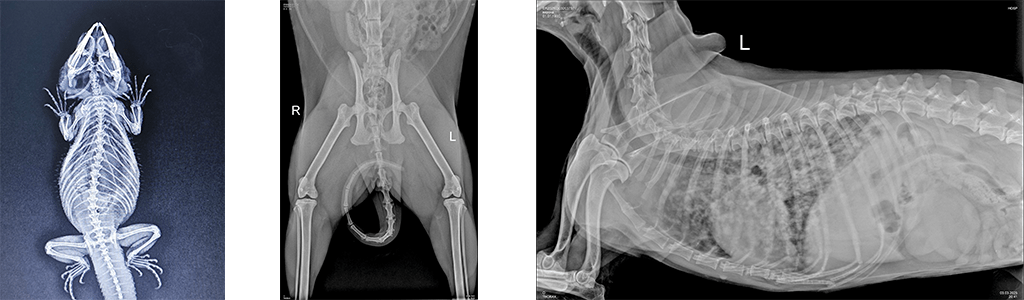

- Рентген-исследование в ветеринарии применяется для определения инородных тел, таких как кости, металлические предметы, резиновые шарики, пули, которые могут находится в самых разных областях тела животного.

- Для исключения патологий опорно—двигательного аппарата: переломов, дегенеративных изменений костной и хрящевой ткани, дисплазии тазобедренного и локтевого суставов, новообразований костей и ряда других патологий.

- Для определения патологий органов грудной клетки: легких, сердца, наличия инородных тел в пищеводе. Рентген-диагностика применяется при таких симптомах у животного, как: проблемы с дыханием, обусловленные наличием воспалительных процессов, новообразований, скоплением жидкости в легких (плевральный выпот); сердечная недостаточность, изменение размеров сердца, например его увеличение или кардиомегалия, пневмоторакс (скопление воздуха в грудной клетке), гидроторакс (скопление жидкости в грудной клетке).

- Рентген головы, челюстей у домашних животных. Здоровье зубов имеет решающее значение для наших пушистых друзей, и рентген челюстей стал неотъемлемой частью ветеринарной стоматологической помощи. Рентгеновские снимки позволяют ветеринарам оценить проблемы с зубами ниже линии десен, такие как, инфекции корней зубов и переломы, которые не видны во время стандартного осмотра полости рта.

- Рентген-диагностика у животных на определение беременности и количества плодов. В отличие от людей, у животных рентген-диагностика активно применяется в случаях, когда необходимо не только подтвердить или исключить факт наступления беременности у животного, но и с большей точностью, чем при УЗ-диагностики, определить количество плодов при беременности. Именно цифровая рентгенография полностью безопасна для самой будущей матери и ее потомства в этом случае.